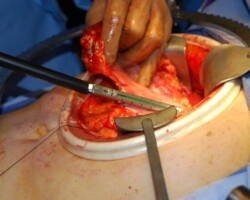

Resection of large retroperitoneal sarcoma including right and transverse colectomy and right hepatectomy